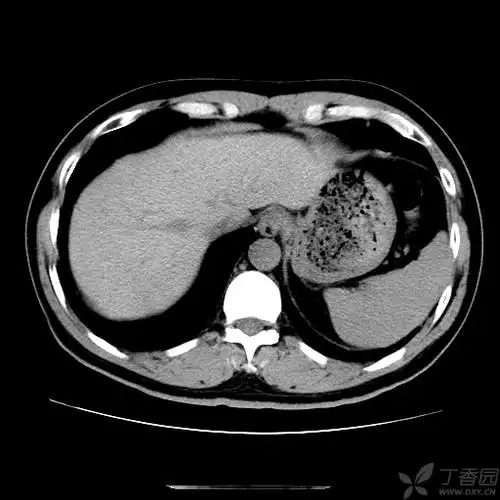

【讨论】肝内胆管轻度扩张,有哪些原因?